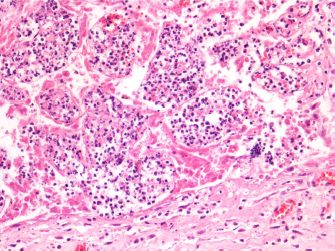

The aborted fetuses and their placentas were delivered to the Department of Veterinary Medicine of Perugia for necropsy and laboratory investigations. Necropsy did not reveal evident gross lesions of the fetuses. Specimens of liver, spleen, lungs, and placenta were fixed in 10% neutral buffered formalin for routine histopathological examination. Samples were embedded in paraffin, sectioned at 4 μm, and stained with hematoxylin and eosin and periodic acid–Schiff to exclude fungal infection. Histopathological examination of hepatic, splenic, and pulmonary samples revealed only parenchymal congestion; placental samples were characterized by diffused congestion of mucosa and submucosal layers with multifocal hemorrhages in the submucosa. Placental villi showed multifocal areas of necrosis associated with neutrophilic infiltration (Fig. 1). Lungs, liver, spleen, placenta, and stomach content were collected for bacteriological investigations.

Fig. 1. Histological section of the placenta. Placental villi are congested and multifocally necrotic with neutrophilic infiltration. Foci of hemorrhages are present in the submucosa. (H&E, 100×).